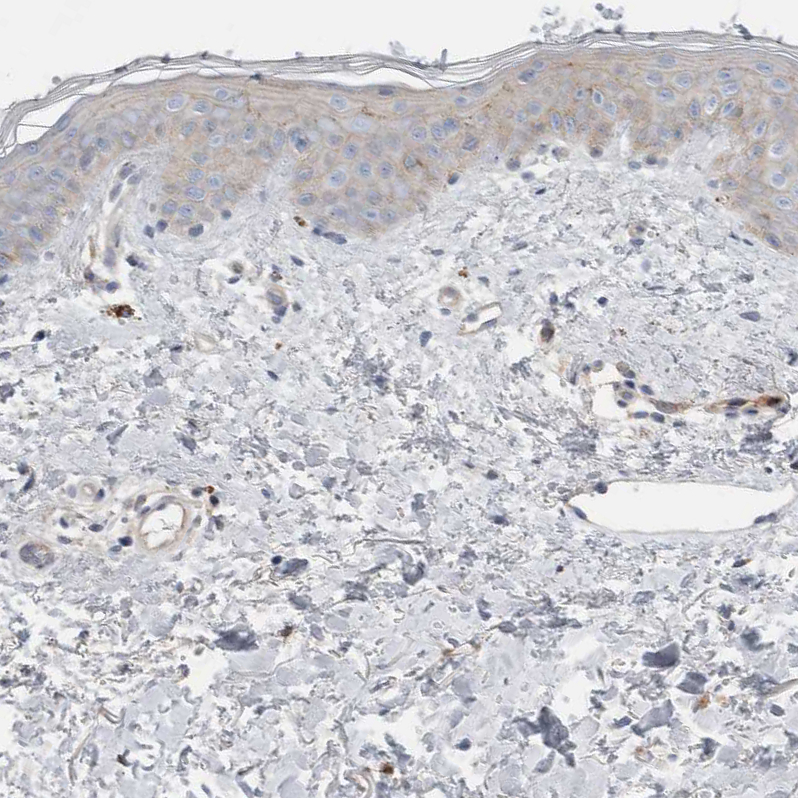

Immunohistochemical staining of human epididymis shows strong positivity in plasma in blood vessels.